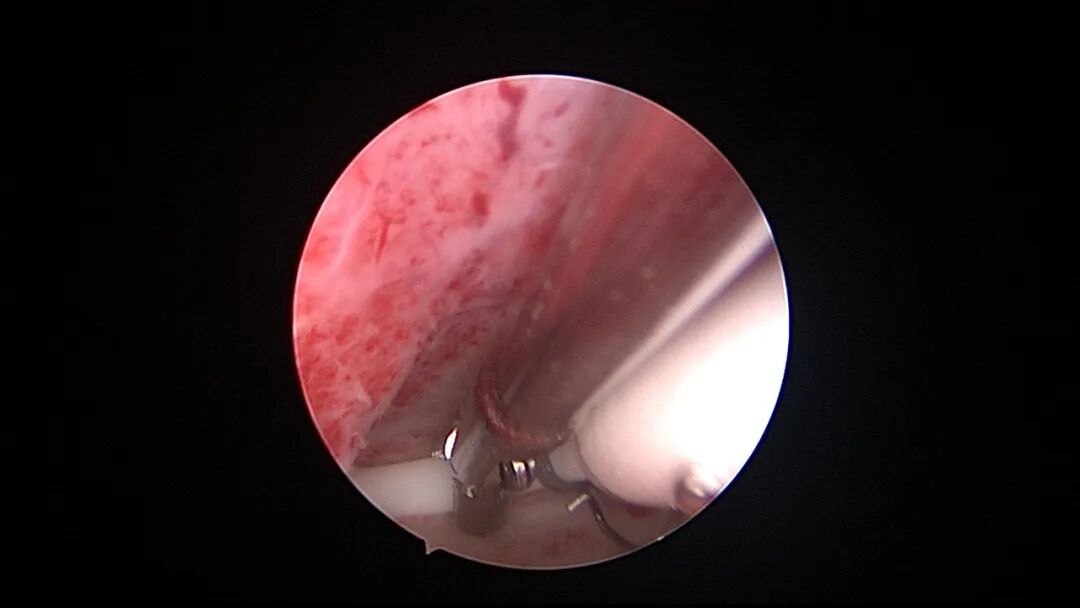

操作步骤描述:宫腔检查镜可完成操作,扩张宫颈至7号扩宫棒,检查镜能轻松通过,避免镜鞘与节育环纵臂在宫颈管形成卡压及筷子效应,影响操作,或卡压摩擦阻力大带出节育环。可用单级电针在宫底扎出小凹坑做标记或作为置入挂钩的隧道(不是必须的)。将挂钩用异物钳直视下送入宫腔,或用中弯钳盲视下送入宫腔,异物钳夹持挂钩将倒钩端插入宫底肌层,越过倒钩。用环尾丝或不可吸收线在节育环顶端打结,形成一个线圈,直径约0.5cm~1cm,结打在线圈旁边,便于夹持操作。将环装回推杆送入宫腔,再夹住节育环固定线圈抵紧宫壁稍旋转就可以将线圈滑进挂钩缺口,挂到挂钩上,可再次向宫底推送挂钩少许,不必夹闭挂钩缺口,重力作用和内膜生长都会阻止线圈脱出,可以用电针电凝挂钩周围组织,进一步防止挂钩脱落。异物钳原位固定节育环,退出宫腔镜,距宫颈外口0.5cm~1cm剪断剩余尾丝。宫颈扩张到9号扩宫棒,冷刀系统异物钳夹持挂钩及线圈也可完成以上操作。

单级电针标记挂钩位置

挂钩固定注意事项:月经干净3~7天手术,此时内膜最薄,利于挂钩固定到子宫肌层,如果内膜较厚,最好用负压吸引器去除内膜,暴露基底层,挂钩才能放置到位,也避免内膜掀起、出血等影响操作。挂钩尖端能轻松在子宫壁上粘附,然后调整钳的位置,将挂钩插入到宫底肌层。也可以在体外连接好挂钩和节育环,同时送入宫腔,异物钳在宫腔夹持挂钩并插入宫底肌层。术后复查B超节育环距宫底距离可能较大,个别达3cm左右,跟子宫大、宫壁厚、外加挂钩长度及线圈长度之和较大有关,保持这个距离不再延长即为手术成功。